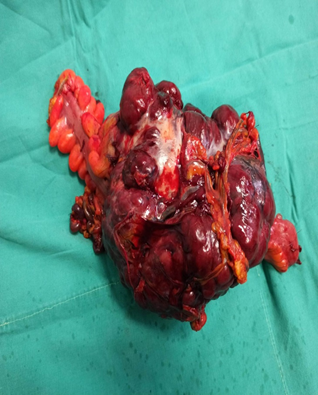

Figure 1 Enormous pelvic solitary fibrous tumor.

Figure 2 Enormous pelvic solitary fibrous tumor.

Severe hemorrhagic tumor maximal diameter 17cm, with enormous collateral net. GIST tumor arising from sigmoid colon infiltrating segment of terminal ileum adjusting with ileocecal anastomosis.

Histopathologic evaluation revealed clinical and immunmorphologically elements compatible with solitary fibrous tumor.